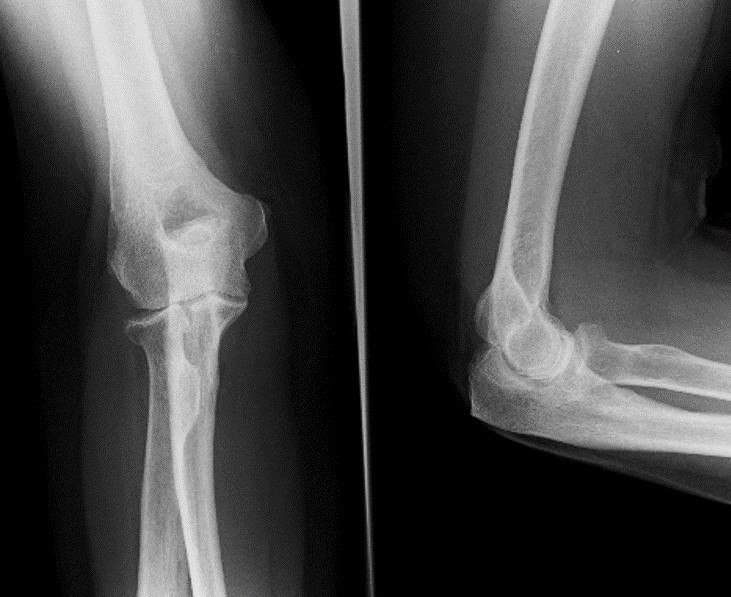

Fractures and dislocations

Distal humerus fracture (complex elbow fracture, GEN)